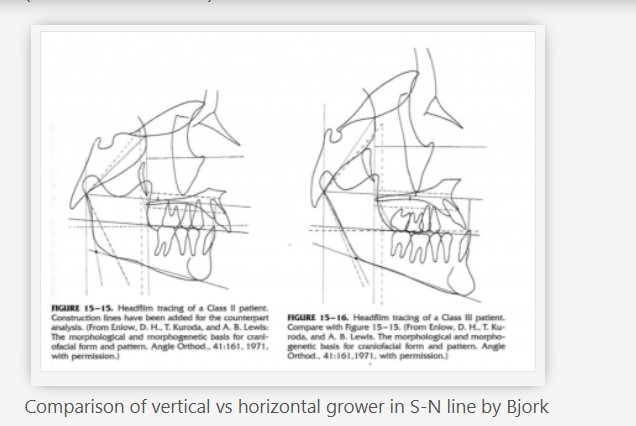

This kinda reminds me of the mew indicator line, indicator cheek line and what'd he go about evaluating SN line, FN plane and Cranial base angles

This kinda reminds me of the mew indicator line, indicator cheek line and what'd he go about evaluating SN line, FN plane and Cranial base angles

View attachment 4063432View attachment 4063433View attachment 4063434View attachment 4063436View attachment 4063438View attachment 4063439View attachment 4063440